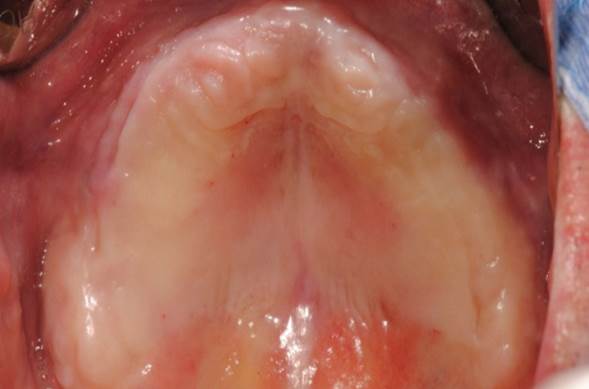

Clinical case: Full-mouth implants for mandibular & maxilla - restored using mixed prostheses

- Courtesy of Dr. Hyun Jun Kim, Korea -

Keywords

AnyRidge, full-mouth implants, mandibular, maxilla, edentulous, full mouth rehabilitation, Octa abutment, long-term clinical case, biological stability, Dr. Hyung Jun Kim

Products:

AnyRidge implant system